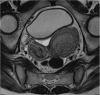

Introduction: Herlyn-Werner-Wunderlich syndrome (HWWS), also known as OHVIRA syndrome, is a rare congenital abnormality of Müllerian duct development characterized by uterus didelphys, unilateral blind hemivagina, and ipsilateral renal agenesis.

Presentation of case: In this report, the authors present the case of a 12-year-old patient presenting with progressive and disabling abdominal pain after the onset of menarche diagnosed with HWWS, describe the various diagnostic modalities and treatment options available, along with a current review of the literature.

Discussion: With normal external genitalia, HWWS is usually asymptomatic until menarche when patients present with worsening abdominal pain during menses and a palpable pelvic or abdominal mass. Untreated, HWWS may lead to a number of complications including endometriosis, infertility, and spontaneous abortion.